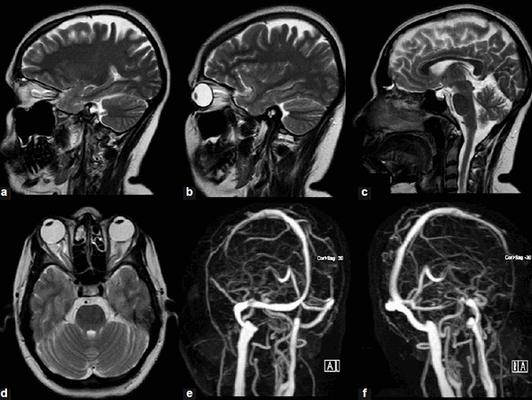

МРТ атеросклероз головного мозга

Атеросклероз сосудов головы лучше всего диагностировать с помощью МРТ сосудов головного мозга или КТ-ангиографии. На томограммах врачам хорошо будут видны дегенеративные изменения в сосудистой системе в виде кальцинирующих бляшек, изъязвлений и смещения тромба и прогрессирующего уменьшения диаметра сосудов.

Признаки атеросклероз на МРТ снимках

У больных с распространенным атеросклерозом системное атеросклеротическое поражение проявляется при проведении магнитно-резонансной томографии аорты с контрастным усилением картиной накопления контраста парамагнетика в аортальной стенке. По характеру накопления выделяются два основных типа: очаговый и диффузно-распространенный тип аккумуляции.

Магнитно-резонансную томографию широко используют в диагностике патологий системы кровоснабжения. При подозрении на атеросклероз МРТ головного мозга назначают для визуализации интракраниальных (внутричерепных) вен и артерий. Сканирование позволяет оценить состояние кровеносных сосудов без инвазивных манипуляций. Исключение - внутривенная инъекция контрастного препарата при магнитно-резонансной томографии с усилением (МР-ангиография).

Снимок артерий головного мозга

Признаки атеросклероза (пораженные участки указаны стрелками) на МРТ